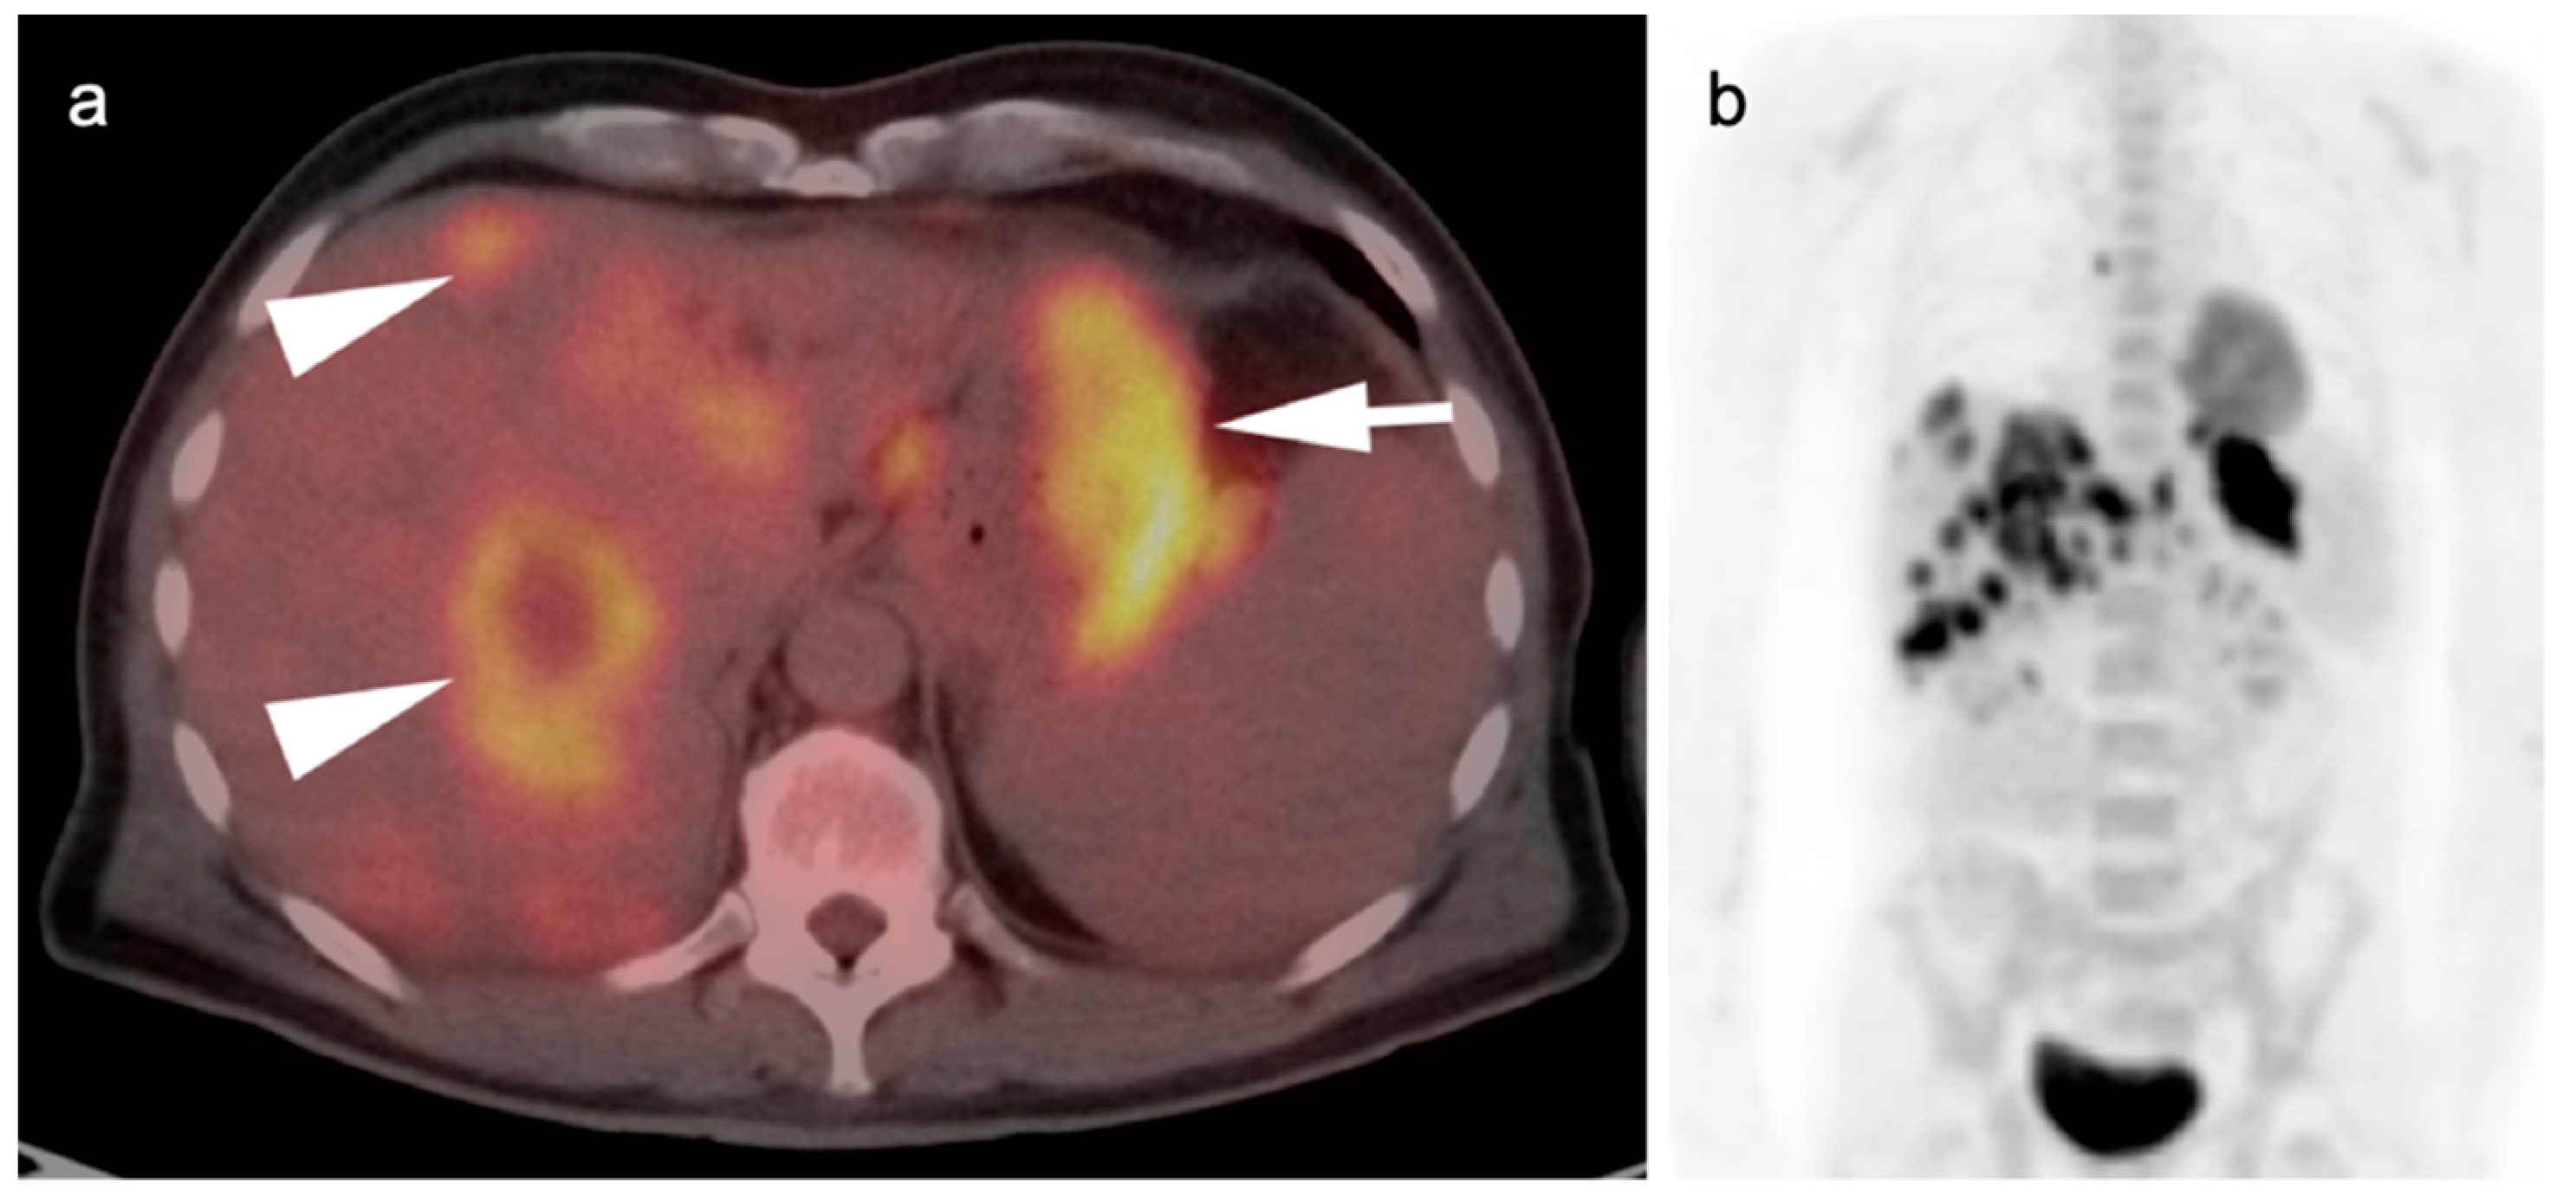

9. Bowel Adenocarcinoma: Colon, Rectum, Small Bowel